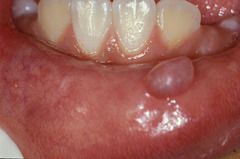

mucocele

-localized tissue swelling that increases and decreases in size most commonly on lower lip -severed salivary gland duct -mucous filled